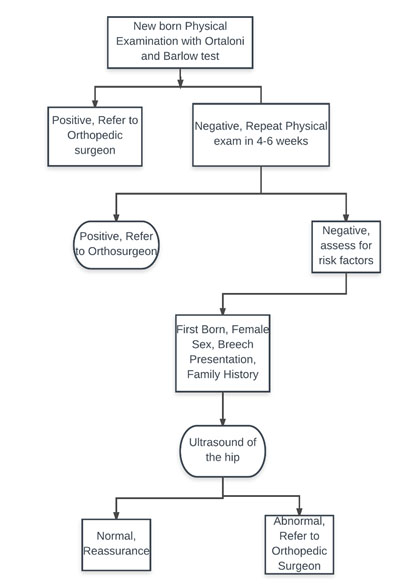

DEVELOPMENTAL DYSPLASIA OF THE HIP

Approach to the referral of DDH patient

WHEN TO REFER

- Any newborn with a click/clunk needs to be reevaluated at 4-6 weeks and if persistent clicks are present refer for Orthopedic review at 4-6 week of age

- Newborn with a frank dislocation

- Ultrasound, which suggests an alpha angle of less than 60 degrees or coverage of less than 50%.

- Any limb length discrepancy with a waddling gait

- Any congenital muscular torticollis, Metatarsus adductus needs review as it has a strong association with DDH as packaging problem

POINTS TO PONDER ABOUT HIP ULTRASOUND

- Any sonologist can make a normal hip abnormal but cannot make abnormal hip look normal

- Needs the expertise to get a proper ultrasound examination

- Most consistent measurements are the coverage, which should be more than 50% and Alpha angle more than 60 degrees.

- Beta angle is a soft tissue measure and not of much use